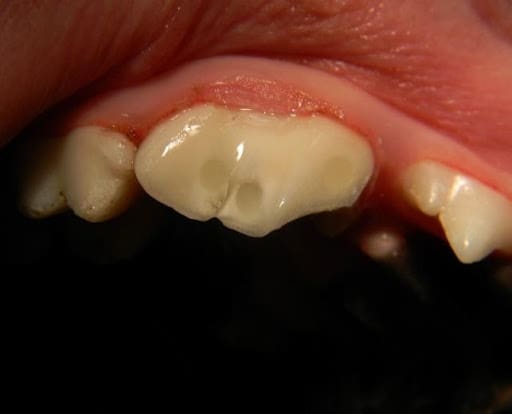

Figure 3 – A previously abscessed upper 4th premolar that has been successfully treated with root canal therapy.

When an endodontic pulp infection takes place there are only two treatment options. Root canal therapy removes the infected pulp tissue and disinfects the pulp canal. The canal is then filled with a dental filling material through a process called obturation. The entrance to the canal is then sealed with dental composite material. Fractured teeth treated with root canal therapy are often prepared for a metal crown which is fabricated and cemented in place about 2 weeks later.

Root canal therapy is most often performed on the most strategically important teeth, including the canine (fang) and carnassial teeth. When this procedure is performed by a veterinary dental specialist, it has a very good prognosis and most often will last the lifetime of the pet.